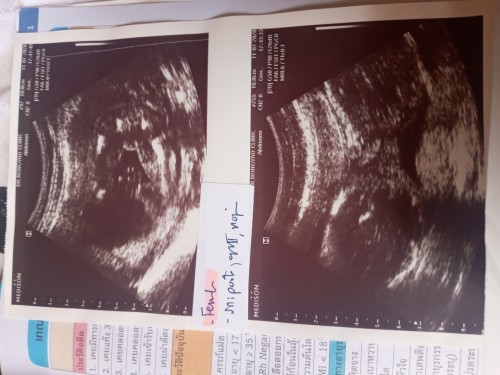

แม่บ้านไหนไปซาว์ดแล้วคุณหมอบอกว่าได้ลูกสาวแล้วคลอดมาได้ลูกชายไหมค่ะแม่แอบกลัวเพราะกรรมพันธุ์ทางคุณพ่อมีแต่ผู้ชายและแม่ไปซาว์ดแค่ครั้งเดียวตอน20wขอดูใบซาว์ดของแม่ๆหน่อยค่ะแม่จะได้เบาใจว่าตรงกับที่แม่แอบหวังไหม

มองไม่ค่อยออกเลยแม่